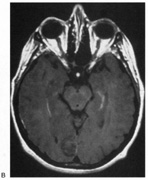

Fig. 15. Bilateral incomplete hemianopia. A 69-year-old man with decreased vision after prostate surgery. A. Fields show remaining central parafoveal vision with some sparing of inferior left quadrant. Note how the defect respects the vertical meridian. B. MRI shows bilateral medial occipital infarction, with sparing of the occipital poles, accounting for the macular-sparing bilaterally. (Courtesy of Dr. Lucia Vaina.)